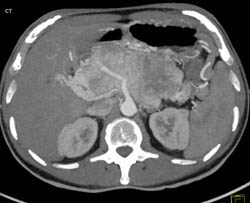

Partial Superior Mesenteric Vein (SMV) Occlusion By Thrombus